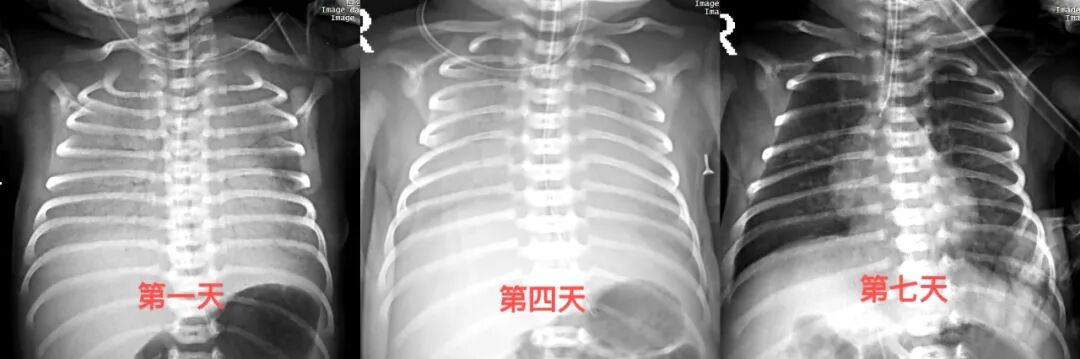

小宝因母亲患有慢性高血压合并子痫前期、瘢痕子宫提前出生。出生初期生命体征平稳,但1小时后突发呼吸困难、血氧骤降,床旁胸片提示新生儿呼吸窘迫综合征Ⅰ期。正当医护人员启动无创呼吸支持时,患儿口吐大量鲜血,诊断为消化道出血。止血治疗刚显成效,病情再度恶化——胸片显示肺部完全变白,呼吸窘迫综合征进展至最危重的Ⅳ期“白肺”,氧合水平一度跌至60%,随时面临呼吸衰竭风险。

气管插管后,患儿气道内涌出大量鲜血,医疗团队立即启用高频呼吸机维持氧合,因白肺难以纠正,生后3天内反复肺内注入肺表面活性物质共3次。经多重病原体核酸检测,幕后“真凶”浮出水面:容易发生多重耐药性的铜绿假单胞菌。新生儿科主任耿艳迅速组织多学科会诊,制定“靶向治疗+精细管理”方案:使用敏感抗生素抗感染、严格限液减轻心肺负荷、精准计算静脉营养支持,并动态调整呼吸机参数。

历经3次胸片危急值预警、1次失血性休克和1次脓毒性休克的生死考验后,小宝的奶量从每3小时1ml逐步增至50ml,体重由2.25kg增长至2.42kg,肺部功能完全恢复。出院时,这个曾游走于生死边缘的小生命,各项指标已接近健康足月儿水平。